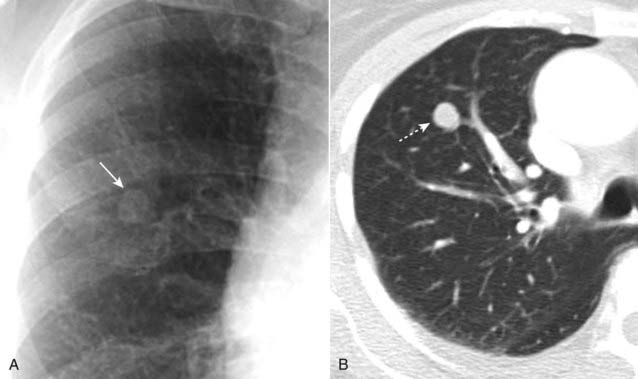

Figure 12-12 Solitary pulmonary nodule, conventional radiograph (A) and CT (B).

A 1.8 cm nodule is seen in the right upper lobe (solid and dotted white arrows) in this 53-year-old male with an episode of hemoptysis. The critical question to be answered in evaluating any solitary pulmonary nodule is whether the lesion is benign or malignant. The answer to the question will depend on many factors, including the lesion’s size and availability of prior imaging studies, which can help greatly in establishing growth of a lesion over time. A PET scan in a lesion of this size might help in indicating if the nodule is benign or not. This patient had a biopsy that revealed an adenocarcinoma of the lung.

Figure 12-13 Right upper lobe bronchogenic carcinoma.

A 3.2 cm spiculated mass is demonstrated in the right upper lobe (solid white arrow). The relatively large size and irregular margins of this mass point toward a malignant process. A percutaneous biopsy revealed an adenocarcinoma of the lung.